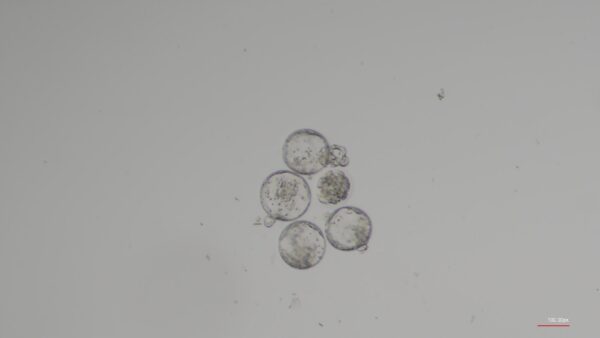

A luta do esperma para chegar ao óvulo foi apenas uma parte das descobertas. Quando os espermatozoides conseguiram chegar aos óvulos, os embriões em estágio inicial que se seguiram, chamados blastocistos, inicialmente pareciam mais fortes do que seus equivalentes concebidos pela gravidade. No entanto, quando a exposição à microgravidade continuou, a qualidade superior dos blastocistos concebidos em microgravidade deteriorou-se e os embriões começaram a ficar atrás dos seus homólogos normais.

McPherson acredita que o ganho inicial de qualidade observado em embriões formados após apenas quatro horas de exposição à microgravidade se deveu ao processo de seleção natural ocorrido, permitindo que apenas os espermatozoides mais aptos chegassem aos óvulos. A deterioração subsequente em embriões que estiveram em microgravidade durante até 24 horas foi provavelmente devida aos efeitos negativos que a ausência de gravidade tem nos processos que ocorrem nas células embrionárias que se dividem rapidamente.